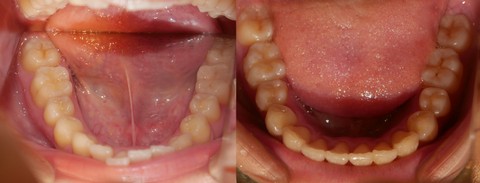

【 出歯、非抜歯、6ヶ月 】

【 出っ歯 をブラケット装着期間 6ヶ月で 】

【 治療期間:2020年7月7日~2021年4月25日、 9ヶ月18日、その中でブラケット装着期間は 6ヶ月13日 】

非抜歯症例